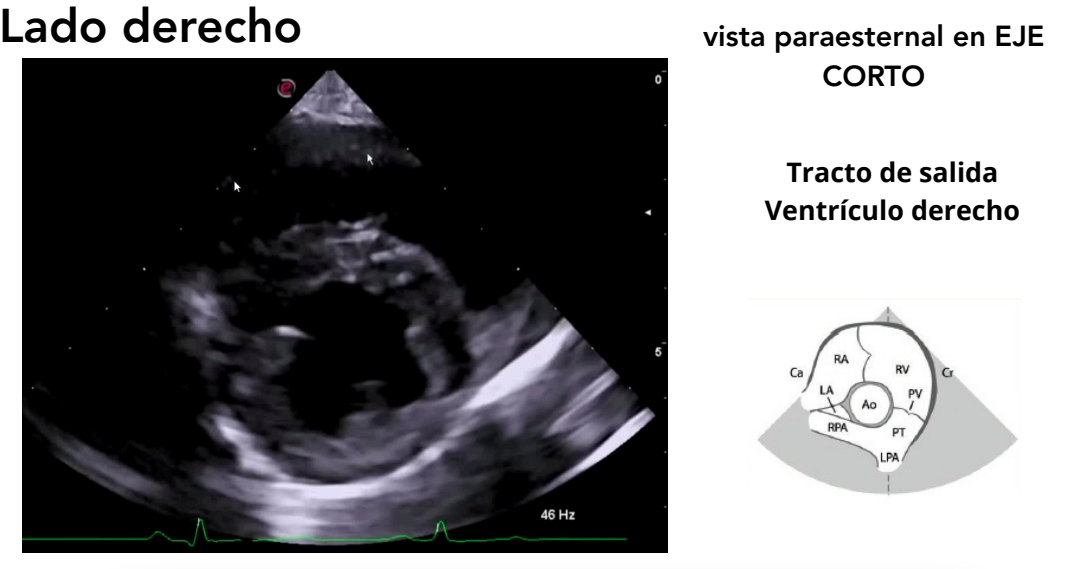

Vista paraesternal en eje corto

- Niveles observables:

- Músculos papilares ("champiñón")

- Válvula mitral ("boca de pez")

- Base cardíaca

- Tracto de salida del ventrículo derecho

Tracto de salida del ventriculo derecho

Modo M: se emplea para medir:

- Diámetro VI (sístole y diástole)

- Espesor del tabique IV (sístole y diástole)